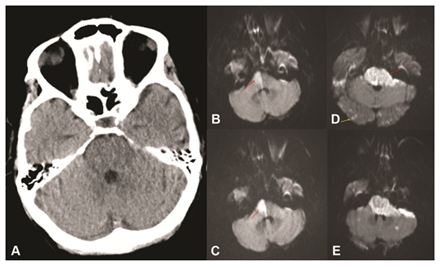

Clinical presentation of CNS fungal infection varies from meningitis, meningoencephalitis, stroke, cerebritis, and vasculitis to venous sinus thrombosis.1,9 CNS fungal infection is difficult to diagnose because of the paucity of laboratory tests for it and its nonspecific imaging and clinical features. The low rate of fungal isolation from CSF specimens can also confound the diagnostic accuracy in these patients.2 Clinical features of fungal meningitis and meningoencephalitis are usually reported as headaches, fever, nausea, vomiting, visual impairment, papilledema, seizure, and acute mental status changes.1 Similar findings were noted in our patient population, with headache being the most common initial clinical presentation. Patients often presented with more than one complaint, not always localized to the CNS. Cerebral vascular accident or stroke-like symptoms such as limb or facial weakness, slurred speech, gait abnormality, or ataxia were collectively the second most common clinical presentation in our patient population. One of the cases was a 68 year old female with high-grade myeloproliferative disorder with acute myeloid leukemia who presented with acute stroke symptoms of hemiparesis, followed by respiratory failure, and stupor. Initial imaging with noncontrast head CT (Figure 1A) showed no acute hypodensity. Subsequent MRI imaging (Figure 1B-1E) showed progressive vertebrobasilar vasculitic infarction of the right pons followed 3 days later by bilateral posterior circulation infarction. LP fluid was negative for fungal organism but autopsy was definitive of fungal progressive invasion of the basilar artery and circulation (Figure 2A-2E).

Figure 1(A) CT head without contrast at onset of hemiparesis which appears negative for bleeding or obvious infarction.

(B & C) MRI DWI sequence showing right upper pontine ischemic changes (C higher cut).

(D & E) demonstrate 3 days later after patient progressed to coma and impaired brainstem reflexes widespread basilar artery territory infarction and scattered diffuse changes in occipital lobes (peripheral) arrow in E which was a higher slice than D.